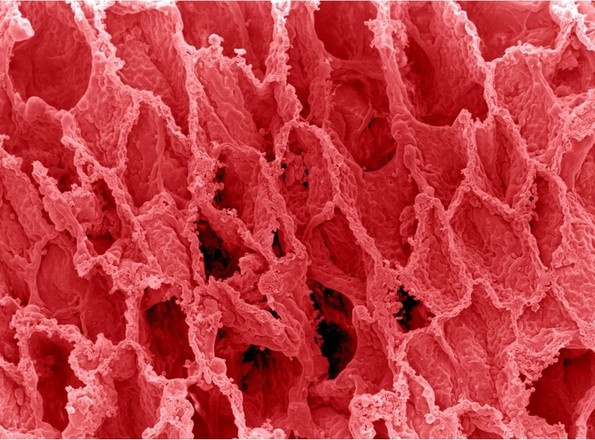

7. Здрави бели дробови